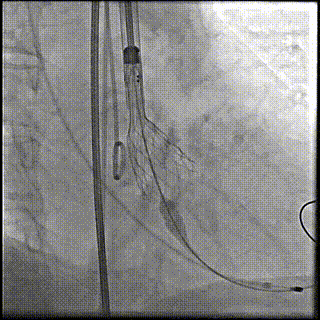

手术影像记录:

主动脉根部造影

22mm球囊预扩

输送器顺利过弓跨瓣